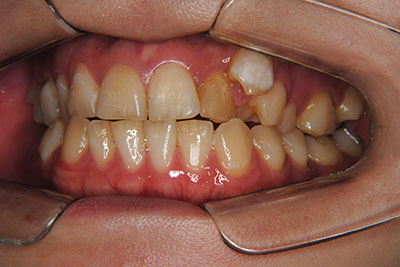

お口の中を診ますと、左上第二小臼歯が歯列の内側に生え、左上犬歯のスペースは全くない八重歯となっていました。検査結果から骨格的な不正はなく。上奥歯が前にずれたかみ合わせで前歯は合っていて出っ歯ではないので左右1本ずつ歯列からはみ出した状態であることがわかりました。上の奥歯を横の歯1本分後ろにずらすことは困難なので、右上中側に生えている第二小臼歯と八重歯である左上犬歯の次の歯=第一小臼歯の2本を抜歯し治療しました。